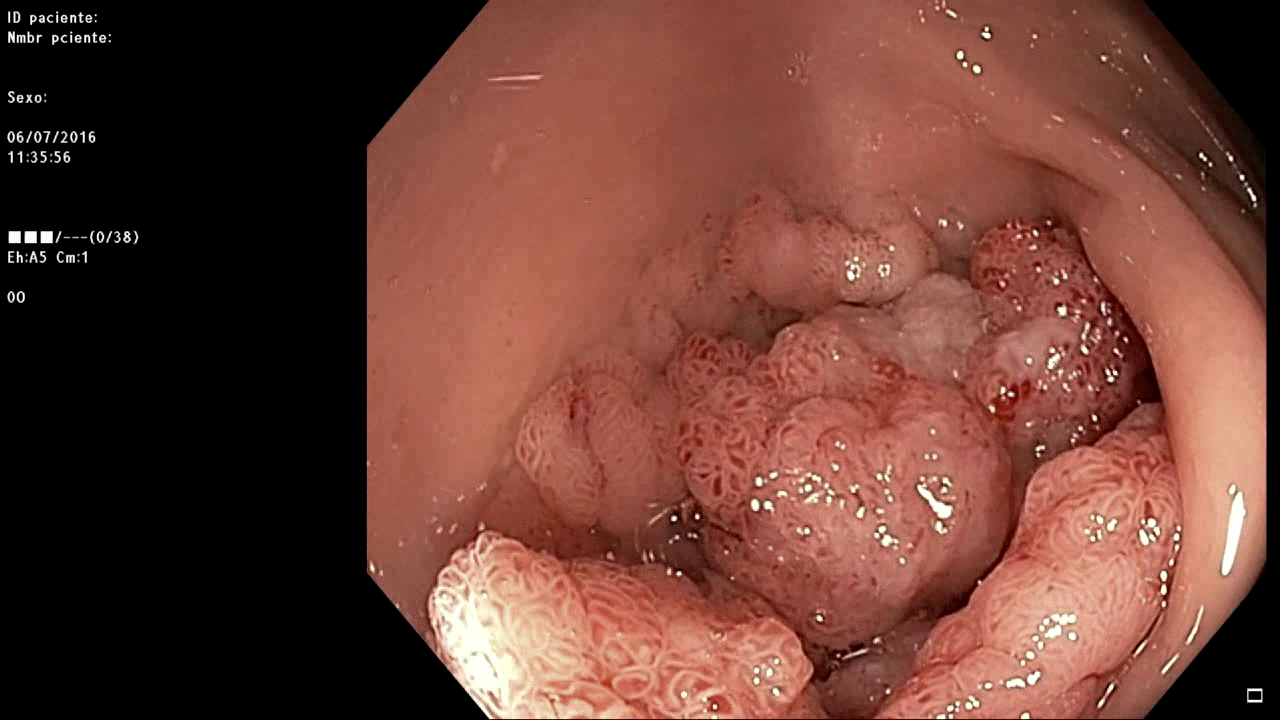

Mujer de 61 años sin antecedentes de interés que presenta rectorragia. En la colonoscopia se aprecia una LST-G de 6 cm de diámetro en el recto que rodea 3/4 partes de su circunferencia y presenta un patrón Kudo IV, NICE 2. El video de la resección se ha editado sólo quitando las partes de intercambio de material, inspección y reevaluación y retirada del material extirpado para poder visualizar lo mejor posible la técnica realizada, inclyendo pequeños errores en la resección y cómo se subsanan. También se ha recortado la coagulación final de los vasos con coagrasper, dejando sólo algunos de los momentos de la revisión final de la escara, aspecto que requiere tiempo. El resultado final anatomopatológico fue de adenoma con componente velloso y DAG. El video se ha editado tras realizar el control a los 6 meses para poder valorar el resultado final. Sobre la zona de la cicatriz se tomaron múltiples biopsias con resultado negativo para adenoma.